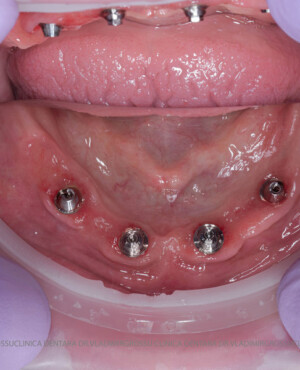

studii științifice.În cazurile de atrofie osoasă severă, când inserarea implanturilor în zonele laterale nu este posibilă fără adăugare osoasă, conceptul All-on-4 prevede plasarea implanturilor în unghiuri strategice pentru a evita zonele deficitare. Astfel, două implanturi sunt plasate în zona incisivilor laterali, iar alte două în zona premolarilor.

- 4 implanturi;

- 2 multiunit-uri drepte și 2 multiunit-uri angulate, conform necesităților protetice;